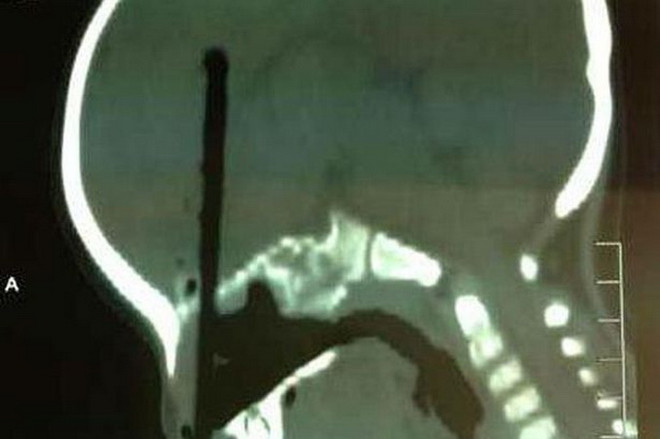

Bé trai bị chiếc đũa đâm sâu vào não do vô tình chọc qua mũi ảnh 1Các bác sĩ phải mất 4 tiếng phẫu thuật để lấy chiếc đũa ra. (Nguồn: Mirror)

Sau 4 tiếng đồng hồ phẫu thuật căng thẳng, các bác sỹ cuối cùng cũng lấy ra được chiếc đũa đã đâm sâu hơn 7 cm vào não cậu bé có tên Huang Zicheng.

Rất may là cái đũa không gây ra tổn thương nghiêm trọng nào cho tế bào não hay động mạch. Cậu bé được hy vọng sẽ hồi phục hoàn toàn.

Bé trai bị chiếc đũa đâm sâu vào não do vô tình chọc qua mũi ảnh 2Rất may chiếc đũa không gây tổn thương nghiêm trọng cho não và động mạch). (Nguồn: Mirror)